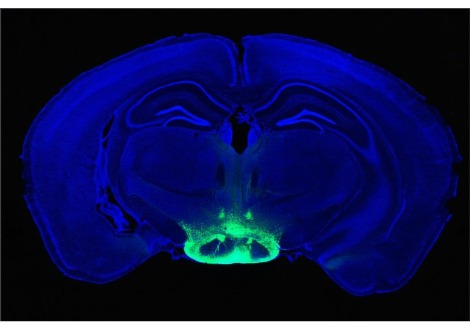

وجدت دراسة جديدة من مختبر البروفيسور آن غريبييل استثناءً مفاجئًا لهذه القاعدة. اكتشف الباحثون أنه في نماذج الفئران لمرض هنتنغتون ، فإن بروتين هوية الخلية MOR1 ، المسمى بمستقبلات المواد الأفيونية من نوع Mu ، يصبح في الواقع أكثر وفرة مع تدهور الخلايا العصبية المخطط لها.

"من المعترف به الآن أن اضطرابات المزاج يمكن أن تسبق الاضطرابات الحركية العلنية لمرضى هنتنغتون بسنوات عديدة. يمكن أن تكون هذه أكثر الأعراض المزعجة للمرضى وعائلاتهم. يقول جرايبيل إن اكتشاف أن هذا المستقبل للمواد الأفيونية يرتفع بشكل كبير في المواقع المرتبطة بالحالة المزاجية في المخطط ، على الأقل في نموذج الفأر الذي يعاني من الاضطراب ، قد يعطي تلميحًا إلى الخلل الوظيفي الأساسي الذي يؤدي إلى هذه المشاكل.

يحيط مستقبل المورفين ، MOR1 (الظاهر باللون السماوي) بمجموعة ممدودة من خلايا المخ (أرجواني) في نموذج فأر لمرض هنتنغتون.